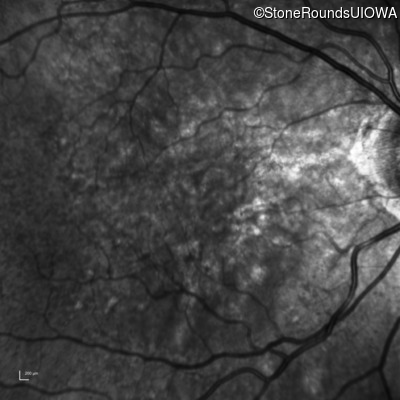

Infrared Fundus Photograph - Left - 20/30 -2 sc

Exemplar